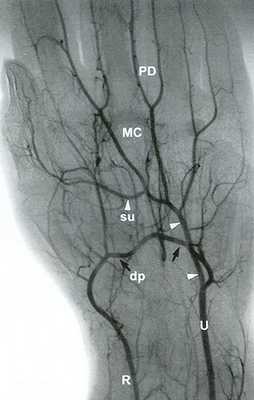

![Рис. 14.5. Лучевая артерия (R) заканчивается глубокой ладонной дугой (dp - черные стрелки)]()

Рис. 14.5. Лучевая артерия (R) заканчивается глубокой ладонной дугой (dp - черные стрелки). Локтевая артерия (V) заканчивается поверхностной ладонной дугой (su - белые головки стрелок). Поверхностная и глубокая дуги обычно сообщаются посредством коммуникантных сосудов, что отражено на ангиограмме. Пястная артерия (МС; также называемая общей ладонной пальцевой артерией или дорсальной пястной артерией) и ладонная пальцевая (РВ) артерия являются ветвями поверхностной и глубокой дуг.